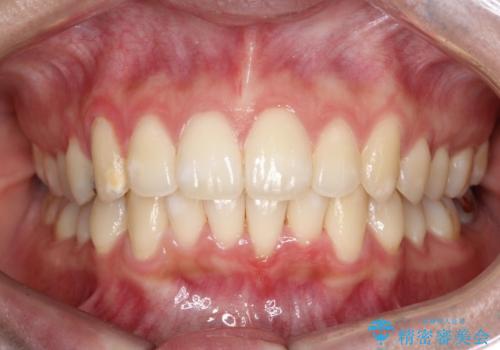

奥歯の噛み合わせは綺麗に噛んでいたため、前歯の叢生(でこぼこ)を、短期間で治療完了するように計画しました。

奥歯の噛み合わせは整っていたため、前歯の並びを美しく修正することに専念できました。マウスピース矯正による治療で短期間で改善しました。

前歯のガタツキを改善する治療法として、マウスピース矯正が適していることが多いです。

マウスピース矯正は、金属製のブラケットやワイヤーを使用せずに、透明なマウスピースを装着して歯を移動させる方法です。そのため、目立たず、痛みも少ないです。